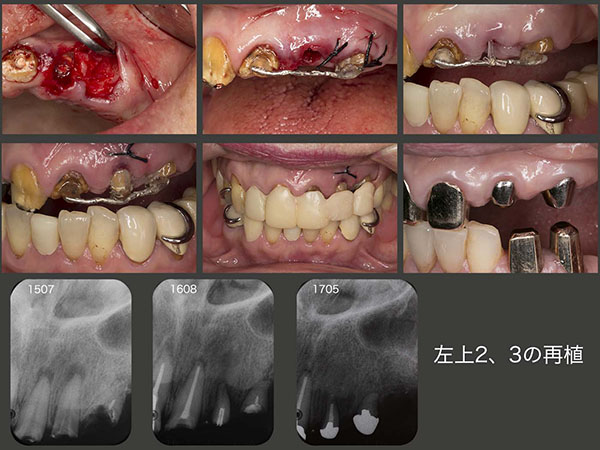

上顎犬歯が左右側にあるか否かが義歯の安定に大きな影響を及ぼすことは自明の理である.左上3は歯根破折しているが,根尖に近い側の歯根膜は健在であることから,再植を行い,うまく生着すれば少なくとも同部の顎堤保存および食感の認知に役立つと思い,実行した.左上2も同時に再植しようと試みたが,なかなか愛護的に抜去できず,このまま突き進めれば歯根破折が生じると思い,一旦中止した.左上3が落ち着いたところで,挺出力をかけ,歯の動揺が生じてから改めて再植した.最終補綴装置は,左上2は根面板,左上3は磁性アタッチメントをそれぞれ装着した.